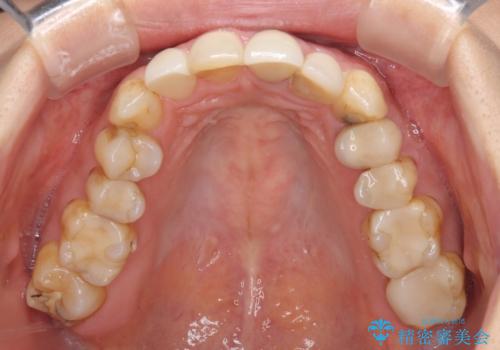

歯肉移植を用いた前歯のオールセラミックブリッジ

- 前歯が折れてしまい、ブリッジによる補綴治療を希望して来院された患者様です。

折れている前歯は抜歯をし、痩せてしまう歯肉は移植術により増大させることで審美面を回復した後、オールセラミックブリッジにて補綴することとしました。

インプラントかブリッジか悩むところでしたが、既に治療されている前歯のクラウン周りの変色が気になっていたため、ブリッジにより色調を合わせたオールセラミックを装着することを選択しました。

歯肉ラインや歯の形態、色調を整えることができ、患者様には大変満足していただきました。